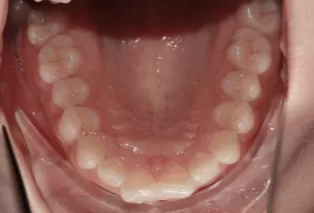

Photos intra-orales